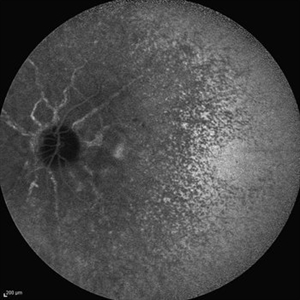

Behcet's Disease Behcet's DiseaseMar 13 2013 by Hamid Ahmadieh, MD Early phase FA of the left eye of a 23-year-old man with retinal vasculitis due to Behcet's disease . Photographer: Solmaz Shahmohammad, Negah Eye Center, Tehran Imaging device: Heidelberg Spectralis Condition/keywords: retinal vasculitis